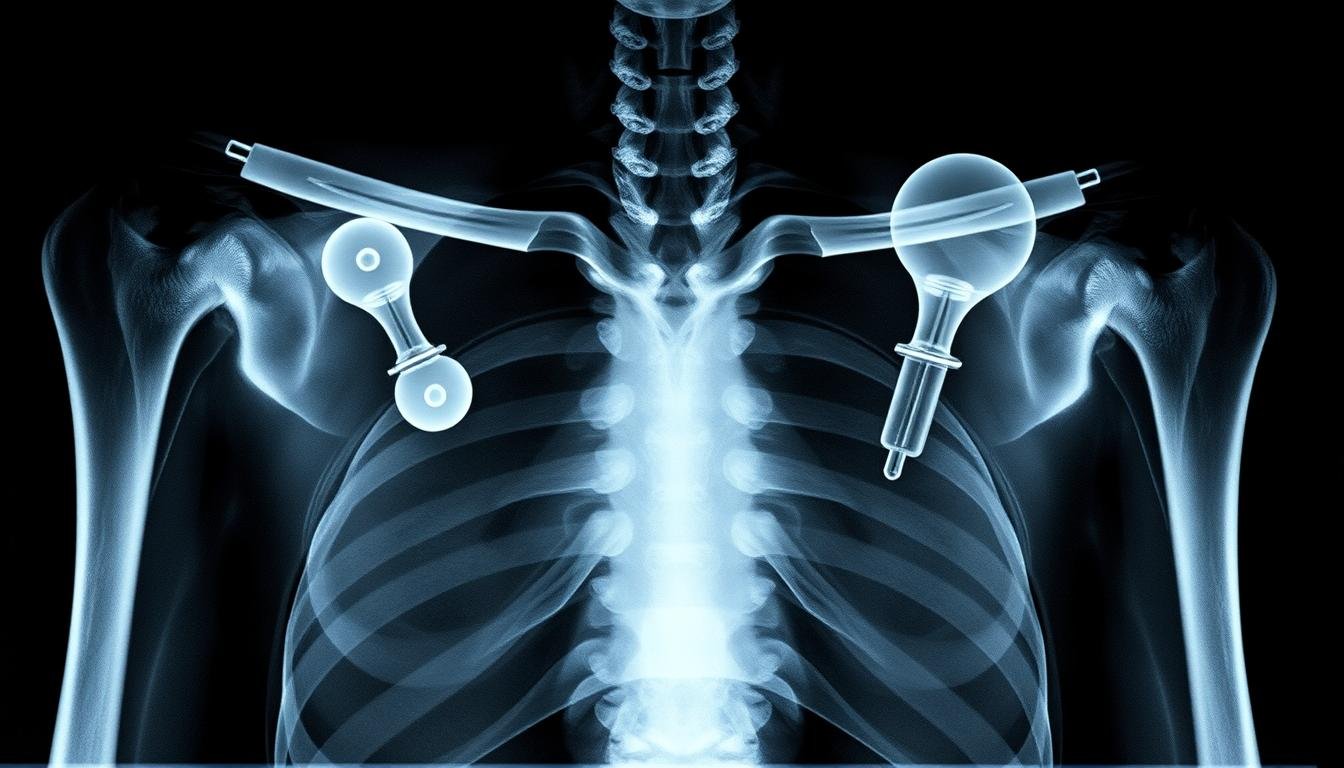

Die inverse Schulterprothese wurde speziell für Patienten entwickelt, bei denen neben der Arthrose auch eine Schädigung der Rotatorenmanschette vorliegt. Die Rotatorenmanschette besteht aus Muskeln und Sehnen, die das Schultergelenk stabilisieren und Bewegungen ermöglichen.

Bei Arthrose mit geschädigter Rotatorenmanschette ist die inverse Prothese besonders geeignet.